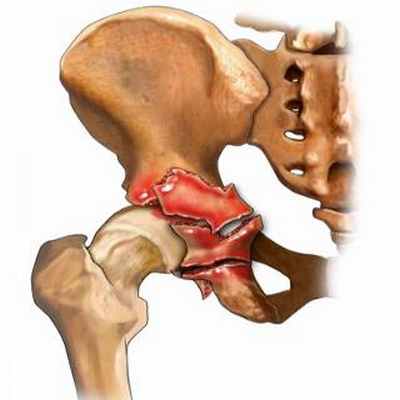

Переломы вертлужной впадины относятся к внутрисуставным повреждениям с долгосрочными нарушениями функции тазобедренного сустава. Успешная репозиция открытым способом и внутренняя фиксация (ORIF) переломов вертлужной впадины со смещением заметно улучшает прогноз при этих весьма разрушительных повреждениях и способствует ранней активизации пострадавшего в отличие от предшествующего метода лечения скелетным вытяжением с постельным режимом на протяжении многих недель.

Выбор доступа зависит от типа перелома и общего состояния пациента. Пространственное представление расположения костных фрагментов является неотъемлемой частью предоперационного планирования. Для предупреждения некроза кости необходимо бережно относиться к мягким тканям. Следует обеспечить защиту жизненноважных нервов и сосудов. Костные фрагменты должны быть с максимальной точностью сопоставлены и стабильно фиксированы, как правило, шурупами и пластинами, которые не должны соприкасаться с суставной поверхностью. Возможность проведения операций под контролем усилителя рентгеновского изображения (ЭОП) позволяет правильно расположить ортопедические металлоконструкции в области вертлужной впадины. По мере накопления опыта оперативного лечения происходит снижение частоты осложнений и неудовлетворительных результатов.

Особого подхода требуют оскольчатые переломы задней стенки и свода ВВ. Сложность заключается в том, что отдельные осколки нужно собрать в единый фрагмент по типу мозаики, а при репозиции в ране (над головкой бедренной кости) отсутствует обзор суставной поверхности вертлужной впадины.

Мы разработали и апробировали способ восстановления суставной поверхности вертлужной впадины при оскольчатых переломах ее задней стенки и свода (Пат. 7229 U Україна, 7 А61В17/56.) [3]. Отдельные костные и костно-хрящевые фрагменты после извлечения из раны сопоставляли и временно фиксировали между собой спицами. Сопоставление фрагментов начинали от периферического отдела. Спицы вводили субхондрально параллельно суставной поверхности от периферии со стороны кортикальной пластинки. Восстановленный таким образом единый фрагмент репонировали и фиксировали к задней колонне пластинкой и винтами, после чего спицы удаляли.

Способ позволяет восстановить сферическую суставную поверхность вертлужной впадины при многооскольчатых ее переломах, обеспечивает оптимальные условия для течения репаративных процессов, исключая дополнительную травматизацию костнохрящевых фрагментов.